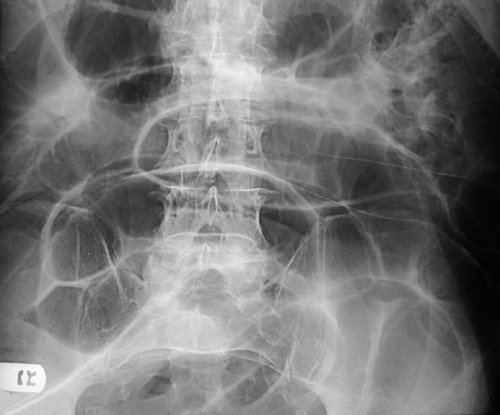

![]() | This abdominal radiograph demonstrates many loops of small bowel dilated with air as a consequence of bowel obstruction from cecal volvulus. In the magnified view below, air-fluid layering is present in the loops of bowel as a consequence of the ileus (lack of peristalsis). |